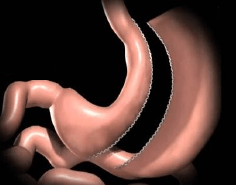

Bypass Gástrico

Es la cirugía con mejores resultados en cuanto a la pérdida de peso y con mayor control de las comorbilidades asociadas a la obesidad, la cual está indicada para pacientes con Obesidad Grado II asociada a otras enfermedades o pacientes con Obesidad Grado III o mayor. Este procedimiento es mediante mínima invasión por laparoscopía, en la que se realiza la formación de un nuevo estómago con una capacidad de 30 - 60 ml, permitiendo tener un efecto restrictivo disminuyendo la ingesta de alimentos y por otro lado se aisla la porción del estómago que produce hormonas que generan hambre por lo que se reduce sustancialmente el apetito. Este nuevo estómago se conecta con un asa intestino delgado, llamada “Asa alimentaria” por la cual transita el alimento ingerido y distalmente se une a otra asa intestinal por la que transita de forma normal bilis y enzimas pancreaticas; sin embargo es hasta que se unen estas dos, en una asa intestinal común cuando se lleva a cabo la absorcion de los nutrientes, de este modo es como se lleva a cabo otro efecto del Bypass Gástrico en la reducción de peso mediante una mala absorción.

El Bypass Gástrico, es una cirugía con mejores resultados en la pérdida de peso y con mejor efecto metabólico permitiendo el control o remisión total de enfermedades como Diabetes Mellitus, Hipertensión Arterial o Dislipidemia. Un punto crucial en este tipo de cirugías es la seguridad, es por ello que llevamos a cabo este procedimiento con la mejor tecnología de material quirúrgico y realizamos pruebas de las uniones gástricas e intestinales mediante endoscopía, reduciendo al máximo la posibilidad de que se presente alguna complicación y permitiendo que el paciente inicie dieta líquida y se movilice fuera de cama el mismo día de la cirugía y sea egresado a las 48 horas de la cirugía en perfectas condiciones, incorporandose a sus actividades a la semana de la cirugía. Los resultados pueden variar en cada paciente y pueden estar determinados por el apego de los pacientes a las indicaciones médicas.